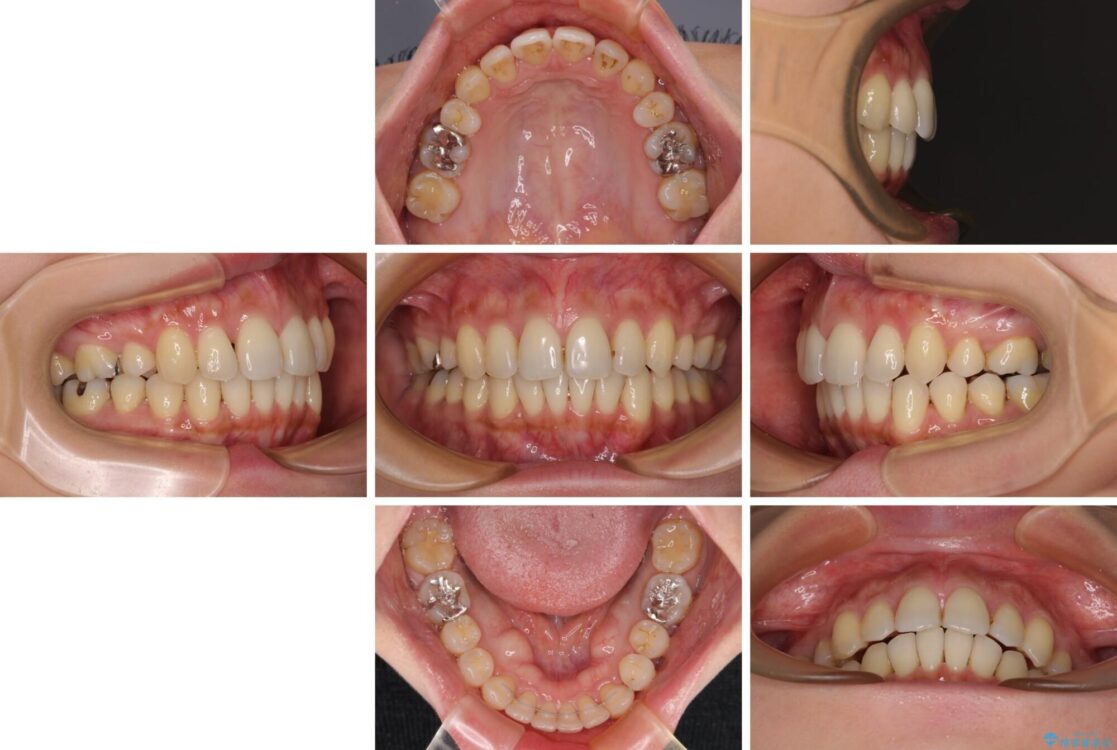

治療後

• 上顎前歯の突出を軽減 インビザラインによる抜歯矯正 治療後画像

インビザラインにて抜歯矯正を行うと、高頻度で奥歯が咬み合わなくなります。

また、抜歯スペースに向けて奥歯が移動する際、必ず傾斜して移動するため、仕上がりの咬み合わせはワイヤー矯正と比べて明らかに劣ります。

抜歯スペースが閉じてからも咬みにくさ改善のためマウスピース矯正を継続するため、治療期間は長期化します。